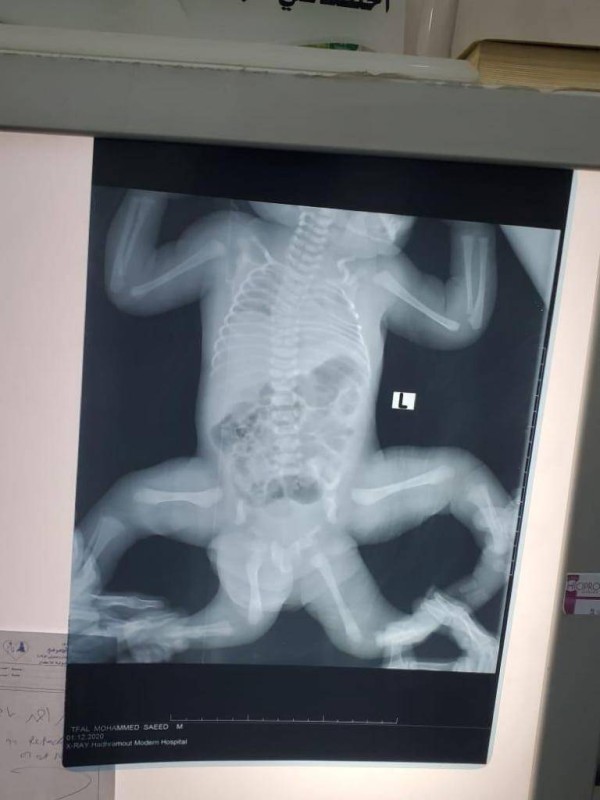

فصائل المقاومة في فلسطين تبارك عملية بركان التي تم تنفيذها في المنطقة الصناعية المعروفة بإسم بركان والذي تم قتل إثنين من الإسرائيليين وأصيب أخر بجروح خطيرة. قناة العالم تنشر خبر فتوى الشيخ ناصر العمر حول جواز مساهدة الافلام الإباحية عبر الانترنت او اي وسيلة اخرى. Jun 29, 2021 · في أقوى تصريح من نوعه، نددت الحكومة بالصمت المخزي من قبل المجتمع الدولي، ازاء الجرائم والانتهاكات اليومية التي ترتكبها جماعة الحوثي ويذهب ضحيتها المدنيين. Jul 03, 2021 · الثورة نت./ نجحت عملية فصل التوأم السيامي اليمني، أحمد ومحمد البخيتي التي أجريت اليوم في العاصمة الأردنية عمان. Jul 04, 2021 · اكدت مصادر طبية في العاصمة صنعاء الخاضعة للحوثيين، نجاح عملية فصل التوأم السيامي اليمني، أحمد ومحمد البخيتي التي أجريت السبت في العاصمة الأردنية عمان.

سهيل نت الرياض نجاح فصل التوأم اليمني عبدالله وعبدالرحمن الرياض نجاح فصل التوأم اليمني عبدالله وعبدالرحمن

نجاح عملية فصل التوأم اليمني بمدينة الملك عبدالعزيز الطبية صحيفة تواصل الالكترونية

بالصور نجاح عملية فصل التوأم اليمني في الرياض